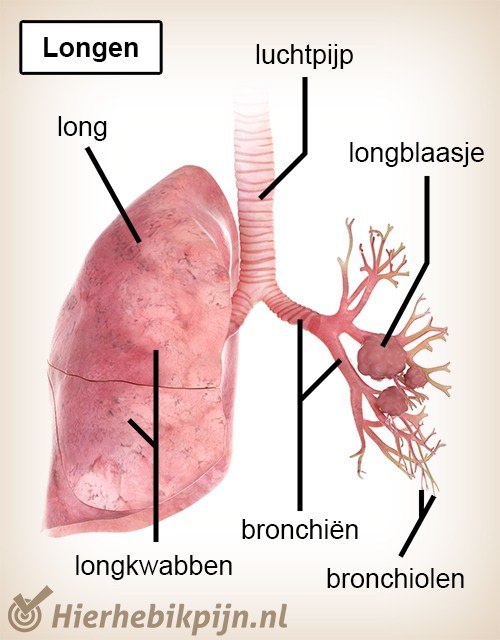

longen Huisartsenpraktijk de Wieke

Longen En Luchtwegen

Longen Mijn Gezondheidsgids

Longen